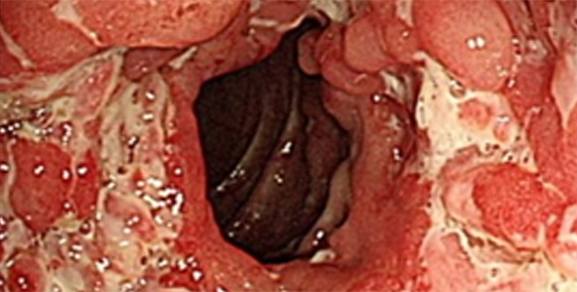

내시경 소견 상 종주궤양이 비연속적으로 나타나며, 조약돌 점막 모양이 관찰됩니다.

크론병이 심화된 상태 4) 크론병의 치료?

아직 완치 가능한 방법은 없습니다.

크론병의 치료 목표는 증상을 완화하고 염증 및 손상된 조직의 파괴를 늦추는 것입니다. 궤양성 대장염의 치료 목표와 같습니다. 우선 약물 치료를 원칙으로 하고, 합병증이 발생하면 수술적 처치를 통해 치료합니다.